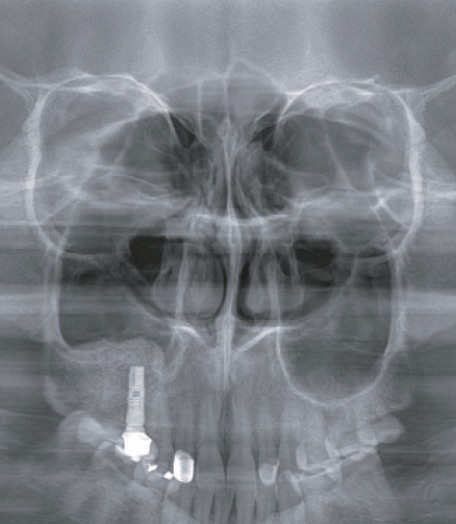

上顎洞撮影

ウォーターズ法撮影